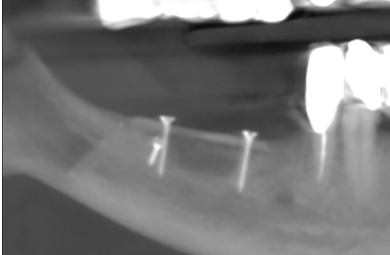

Considerando las características del caso, se realizó en un primer tiempo la exodoncia del diente 45 y la explantación de ambos implantes, además de eliminar el proceso infeccioso subyacente. La intervención y el postoperatorio transcurrieron con normalidad y el paciente recuperó la sensibilidad del labio durante el mes siguiente a la intervención. Cuatro meses después de la cirugía inicial, se solicitó un nuevo CBCT para valorar el defecto óseo remanente (Figura 2).

Cinco meses después, se efectuó un nuevo CBCT para evaluar la ganancia ósea conseguida. En el estudio tomográfico pudo observarse una ganancia media vertical de 6,4 mm y una ganancia media horizontal de 7,8 mm, lo que sumado al hueso remanente permitió colocar dos implantes Klockner® KL RP de 4 x 10 mm en 46 y 47 a 35 N/cm2 (Figuras 8-12). El diente 45 se decidió rehabilitar mediante un póntico en extensión para prevenir la lesión del nervio mentoniano durante la inserción de los implantes. La segunda fase se realizó a los tres meses de su colocación. Tras la cicatrización del tejido blando, se tomaron las impresiones mediante el escáner intraoral Carestream Dental CS 3600 y se realizaron las restauraciones protésicas finales con tecnología CAD/CAM (Figuras 13 y 14).